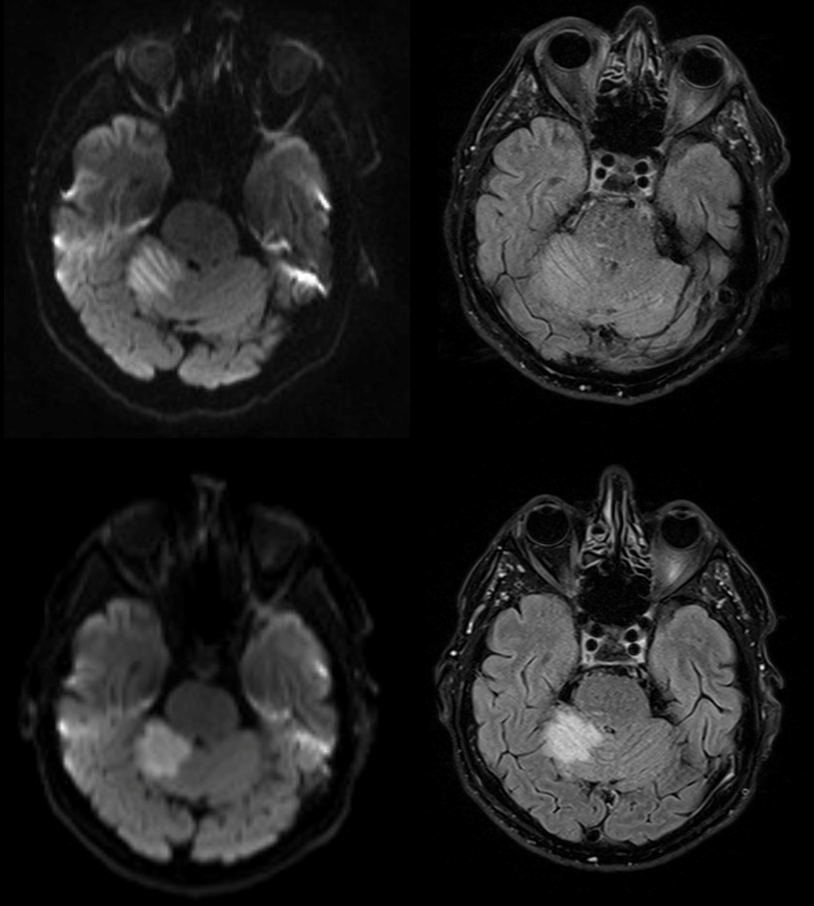

Jako specjalista neurolog zajmuję się diagnostyką i leczeniem przede wszystkim stwardnienia rozsianego oraz innych chorób demielinizacyjnych, a także migreny i innych bólów głowy.

• udar mózgu,